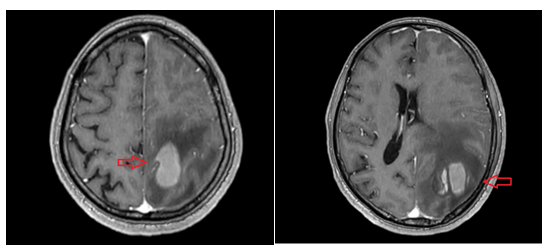

CASE LÂM SÀNG Điều trị bệnh nhân mắc đồng thời hai loại ung thư: Ung thư phổi và ung thư tuyến tiền liệt

CASE LÂM SÀNG Điều trị bệnh nhân mắc đồng thời hai loại ung thư: Ung thư phổi và ung thư...